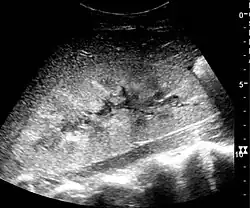

One of the primary indications for referral to US evaluation of the kidneys is evaluation of the urinary collecting system. Enlargement of the urinary collecting system is usually related to urinary obstruction and can include the pelvis, the calyces and the ureter. Hydronephrosis is seen as an anechoic fluid-filled interconnected space with enhancement within the renal sinus, and normally, the dilated pelvis can be differentiated from the dilated calyces.[1]

The hydronephrosis is typically graded visually and can be divided into five categories going from a slight expansion of the renal pelvis to end-stage hydronephrosis with cortical thinning (Figure 15). The evaluation of hydronephrosis can also include measures of calyces at the level of the neck in the longitudinal scan plane, of the dilated renal pelvis in the transverse scan plane and the cortical thickness, as explained previously (Figure 16 and Figure 17).[1]

If the fluid in the dilated collecting system has echoes, pyonephrosis should be excluded by clinical exam, blood analysis and, in special cases, puncture or drainage. Hydronephrosis can also be caused by non-obstructive conditions, such as brisk diuresis in patients treated with diuretics, in pregnant women and in children with vesicoureteral reflux.[1]